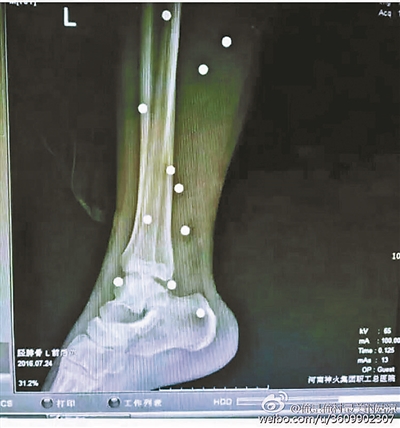

傷者體內取出的鋼珠

爆炸導致鋼珠遍布傷者身體各處

黃明的伯伯對北青報記者表示,由于黃明直接踩到了爆炸物,所以傷情最為嚴重,“他的腿被炸斷,身體內被炸進了40多顆鋼珠。手術后已經從體內取出29顆鋼珠,還有十多顆鋼珠沒有取出來?!备鶕S明的入院記錄,他全身有多處爆炸傷,且全身多處異物存留。

爆炸發(fā)生時,陳浩的位置與黃明靠得很近,因此也受傷較重。他告訴北青報記者,經過10多個小時的手術后,醫(yī)生從他身體里取出了12顆鋼珠。目前,他和黃明兩人經過手術后,已從重癥監(jiān)護室轉至普通病房。其余三人中,陳剛的臀部受傷,當天晚上在醫(yī)院清理完傷口后便回了家,而同行的兩名女生身上有一些擦傷。